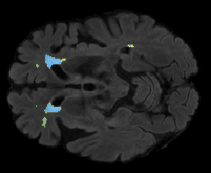

We evaluated our method in segmenting WMH from T1-w images using: a) Synthesized FLAIR images by treating the synthesis as a preprocessing step – we will refer to this method as offline synthesis; b) Synthesized FLAIR images using the proposed method, and c) without any synthesis – we will refer to this method as Unimodal. Baseline methods are illustrated in Figure 2

Table 2: Segmentation results for all proposed methods, each column represent a different slide in the image, blue areas are regions which were correctly labeled, false positives are shown in green, and false negatives in yellow

In order to better understand the above results, we visually analyzed the output segmentation performed for each method. Table 2 shows the results for three different slices (one slice per column). As illustrated, the proposed method is able to produce less false positives. It is also important to note that, unimodal segmentation is the one that produces more false positives, showing the advantage of using synthetic data. Regarding the nature of false positives, it can be easy to see in the third column a large number of false positives are on the border of periventricular lesions for the Unimodal method in comparison to the proposed method. Also from the first and second column, it can be observed that Unimodal tend to produce more small regions of false positives near to cortical areas. Removing such false positives requires additional post-processing steps, therefore, it is of value avoid this kind of over-segmentation. It can also be noted that synthesis methods tend to produce the same kind of false negatives, this may be due to the blurring effects in synthesized images since the information available during testing is limited – which otherwise is available from a FLAIR sequence.